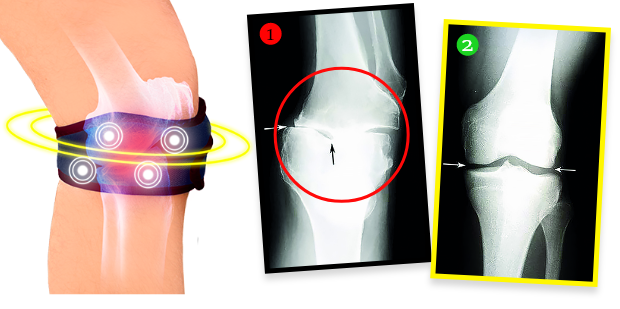

Gospođa Marija je nakon tretmana napravila rendgensku snimku i pokazalo se da su se degenerativne promjene u koljenu potpuno povukle! Liječnik je ostao zapanjen – nije znao što reći. A činjenice govore da je zahvaljujući biomagnetskom stezniku stanje koljena gospođe Marije doživjelo pravi preporod. Ne samo da se prestalo pogoršavati, već se dogodilo nešto nevjerojatno. Hrskavično tkivo i osjetljive strukture unutar zgloba obnovili su se, a koljeno je povratilo punu pokretljivost kakvu je imalo prije mnogo godina. Steznik, naime, emitira prirodno i sigurno biomagnetsko polje koje prodire u najdublja tkiva zgloba, hraneći i regenerirajući hrskavicu, vraćajući joj elastičnost i gipkost, a također potiče proizvodnju sinovijalne tekućine koja ublažava udarce i štiti od bolnog trenja tijekom kretanja. Ovo je potpuno neinvazivan i siguran tretman.